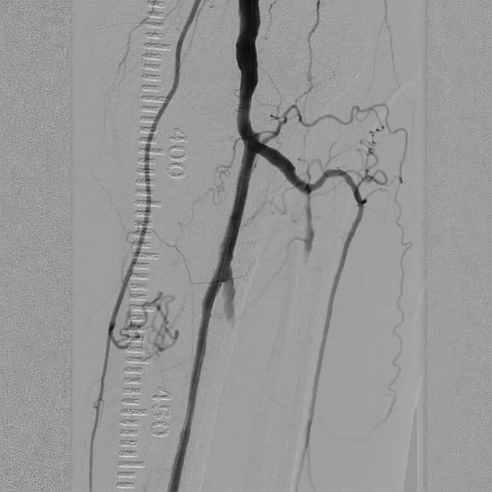

造影显示左侧胫腓干动脉闭塞,胫后动脉通过侧支循环显影,左侧腓动脉及胫前动脉全程闭塞。

选用2×40mm普通球囊扩张闭塞病变,造影可见局部内膜撕裂严重,形成明显夹层(提示病变坚硬,需支架支撑)。